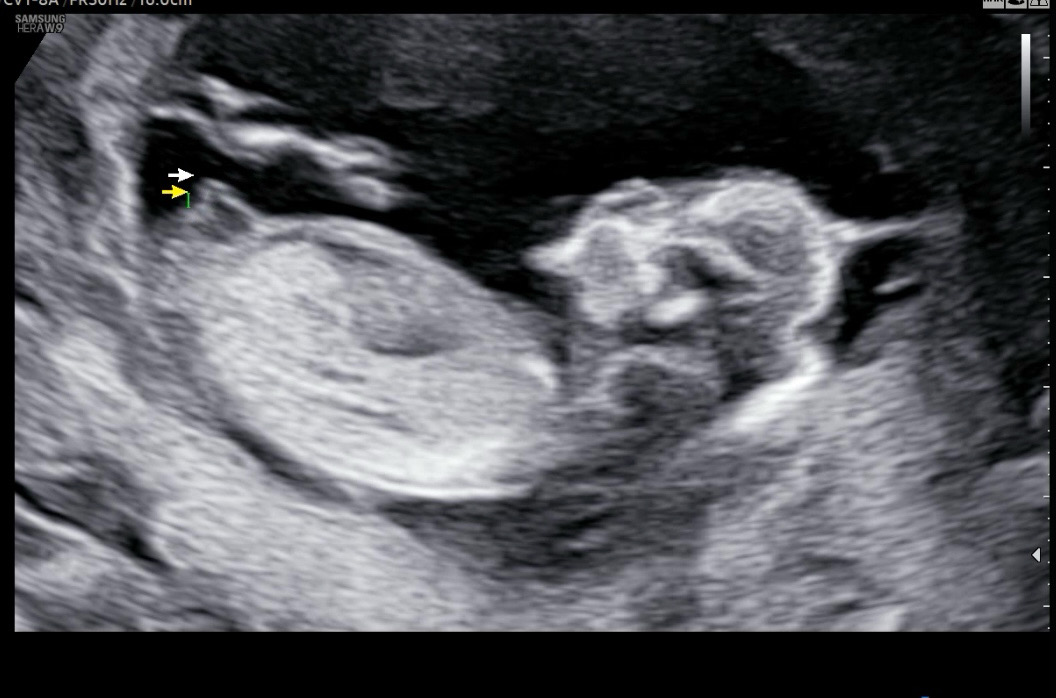

13주차에 튀어나온게없다는 힌트 받았는데! 봐주세용

튀어나온게 없다구 힌트가 됬냐고 하시는데 이정도면 딸 확정일까유?

평행한걸보니 딸같아용 ㅎㅎ